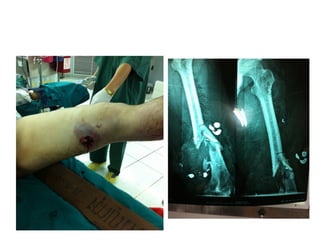

ชายไทยนักเลง อายุ 32 ปี ละแวกตรอก

จันทน์ สะพาน 3 ถูกคู่อริยิงเข้าที่ต้นขาซ้าย

เดินมาโรงพยาบาลหลังเกิดเหตุ 30 นาที

Ext : wound was described as picture

ABI 1.3